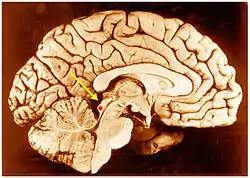

Inferior colliculus (red dot) in human brain, sagittal section.